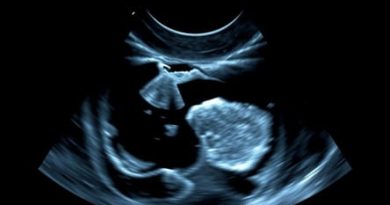

Ultrasound For Capsular Contracture Near Me

Capsular contracture is a common complication following breast augmentation or reconstruction surgery, characterized by the hardening and tightening of scar